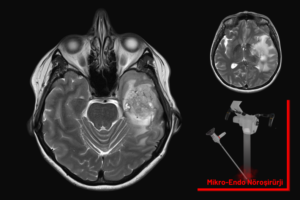

Beyin tümörü ameliyatı, beynin içindeki tümörlü dokunun çıkarılarak sağlıklı beyin fonksiyonlarının korunmasını ve hastanın yaşam kalitesinin artırılmasını amaçlayan hassas bir cerrahi işlemdir.

Beyin tümörü ameliyatı, tümörün çıkarılırken sağlıklı beyin dokusunun korunmasına özen gösterilen hassas bir cerrahi işlemdir.